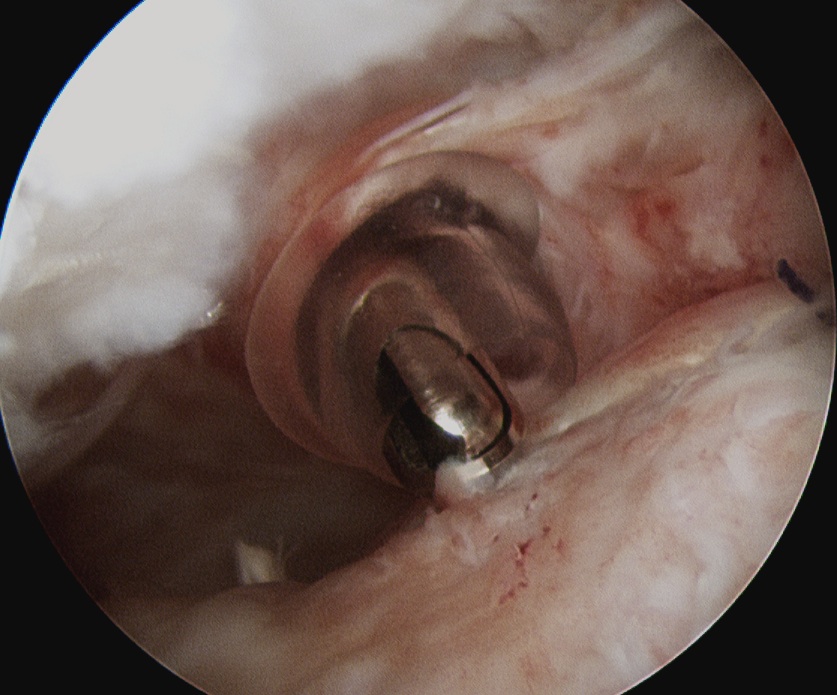

GHJ

- identify tendon

- grasp, forms comma sign

- perform biceps tenodesis

- tag SSC with fibrewire